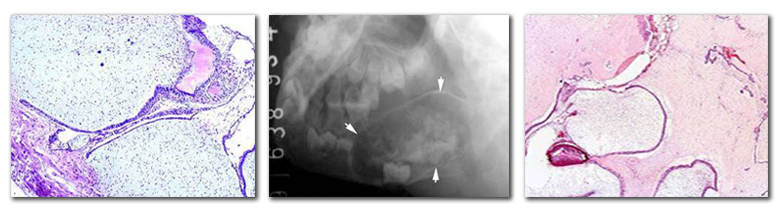

◇ 光镜观察:上皮和间充质两种成分组成;肿瘤上皮呈条索状或团块状排列,类似于成釉细胞瘤;间叶成分由较幼稚的结缔组织组成,细胞丰富,类似于牙乳头细胞;上皮与结缔组织之间狭窄的无细胞带,玻璃样变的透明带。

多见于儿童和青年人,平均年龄为15岁;常见于下颌磨牙区;肿瘤生长缓慢,引起颌骨膨大;X线表现为界限清楚的放射透光区,与成釉细胞瘤不易区别。

◇ 混合性牙瘤:儿童和青年上下颌骨均可发生,下颌前磨牙区和磨牙区多见。境界清楚的放射透光区,放射阻射性结节状钙化物。牙体组织成分排列紊乱相互混杂,发育期混合性牙瘤与成釉细胞纤维牙本质瘤和成釉细胞纤维牙瘤不易区别。生长有自限性。